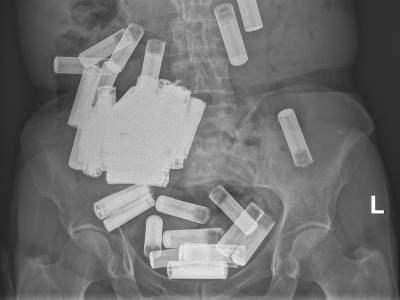

Lekari izvadili preko 50 baterija iz stomaka jedne žene